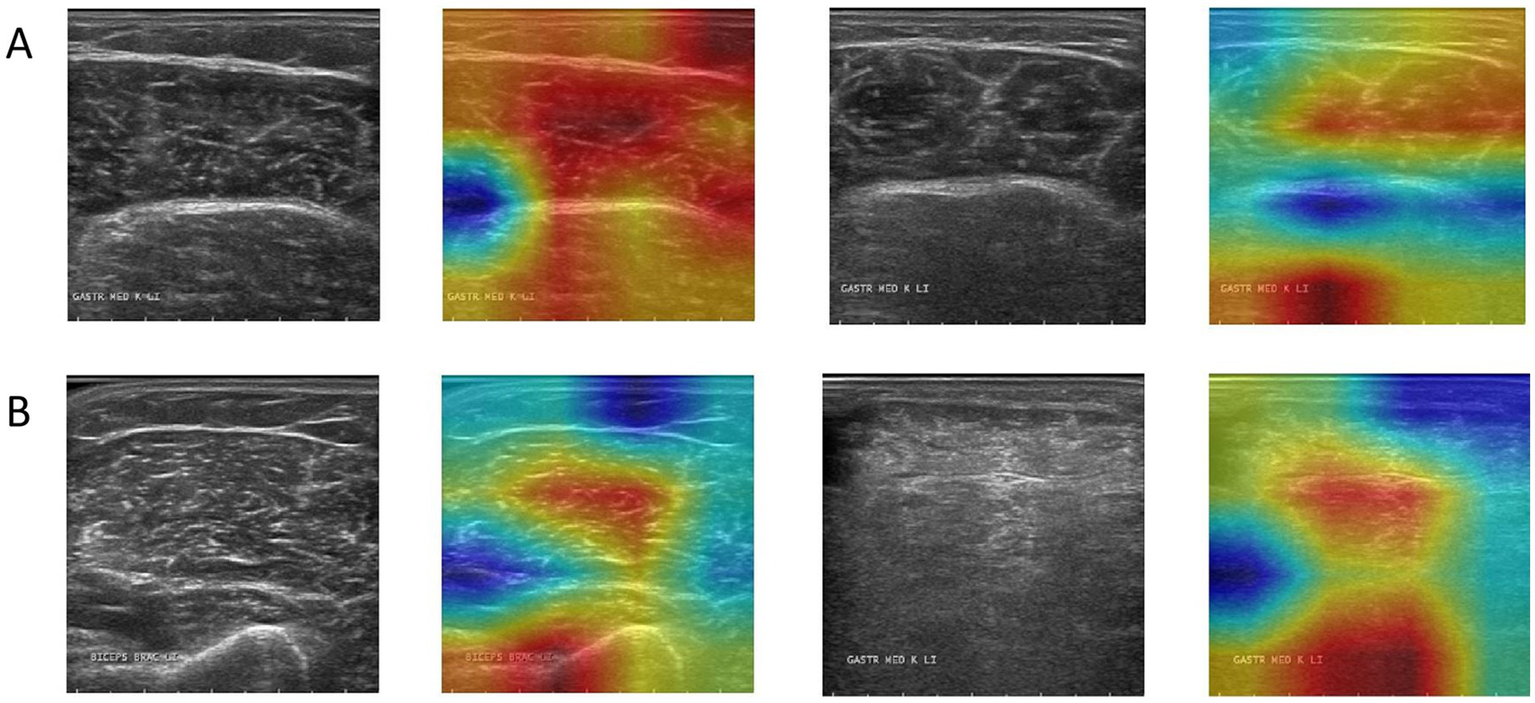

Grad-CAM was used to visualize the model’s focus areas on typical healthy and pathological muscle images (Figure 6). For healthy samples (Figure 6A), the high-response areas in the heat map concentrated on the transverse stripe-like texture corresponding to neatly arranged muscle fibers. For the pathological sample (Figure 6B), the high-response areas focused on regions with disordered echoes, blurred edges, or focal hypoechoic areas. These visualized regions correspond to locations of known pathological features.

Figure 6

Grad-CAM activation heatmap visualization, where (A) represents healthy samples and (B) represents abnormal samples.

We evaluated model performance using several quantitative metrics, including accuracy, precision, recall, F1-score, and the area under the curve (AUC). Accuracy measures the proportion of correct classifications and is the basic indicator for evaluating overall performance. Precision (also known as positive predictive value, PPV) is used to evaluate the proportion of the model’s predictions of the “pathology” category that are actually pathological, reflecting its ability to control false positives. Recall measures the model’s ability to identify pathological samples and reflects the risk of missed diagnosis. The F1-score, as the harmonic mean of precision and recall, is suitable for scenarios with uneven sample distribution. Finally, the AUC value reflects the stability and discrimination ability of the model at different decision thresholds and is an important basis for evaluating the generalization performance of the model (23). In addition to these quantitative metrics, we qualitatively assessed the model’s interpretability using Gradient-weighted Class Activation Mapping (Grad-CAM), a technique that generates a visual heatmap to identify the image regions most influential for the model’s classification decision. In these visualizations, the heatmap is used for a qualitative assessment of the model’s focus. Warmer colors (e.g., red) indicate regions that were more influential in the model’s classification decision, while cooler colors (e.g., blue) represent areas of lesser importance. This approach helps to interpret where the model is looking, rather than quantifying the precise importance of each pixel.